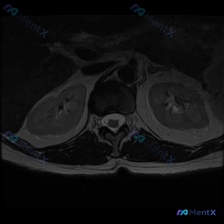

看到一个挺有警示意义的读片场景,整理出来和大家分享一下。 基本临床场景 临床怀疑患者存在椎间盘病变,提供了一张T2加权冠状位磁共振影像,请读片判断是否存在椎间盘病变,拿到的影像分析结果如下: 现有影像分析内容: 1. 双侧肾脏轮廓清晰,位置大小正常,肾周脂肪间隙清晰,无渗出模糊影 2. 肾脏皮髓质分...

看到这个读片需求,整理了完整的分析思路分享给大家。 病例基础信息 用户提供一张腹部MRI轴位T2加权图像,问题是:判断这张影像上是否存在椎间盘病变。 第一步:影像基础评估 先给大家整理这份影像的客观发现: 1. 图像质量:对比度良好,能清晰显示腹膜后结构,无明显运动伪影 2. 解剖定位:这是上腹部/...